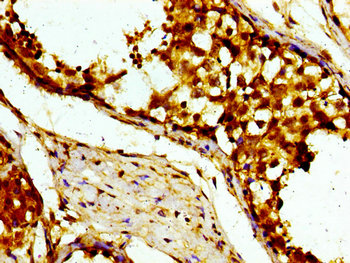

CSB-PA613516LA01HU

Immunohistochemistry of paraffin-embedded human testis tissue using CSB-PA613516LA01HU at dilution of 1:100